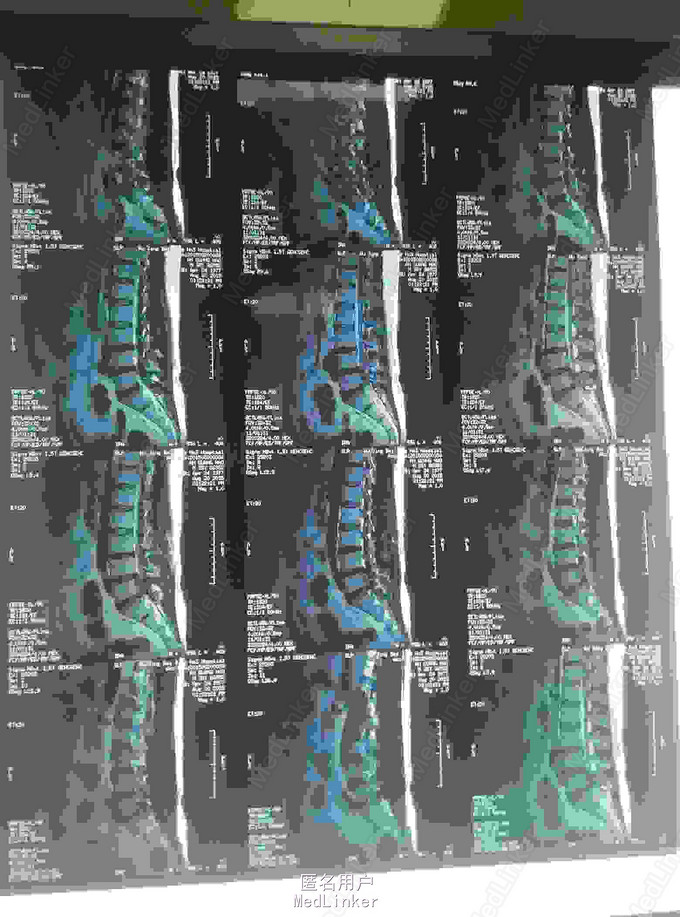

腰椎间盘突出

腰痛伴左下肢疼痛麻木3年

椎间盘突出穿破后后纵韧带游离到硬膜囊背侧

腰椎间盘突出,腰椎间孔镜治疗